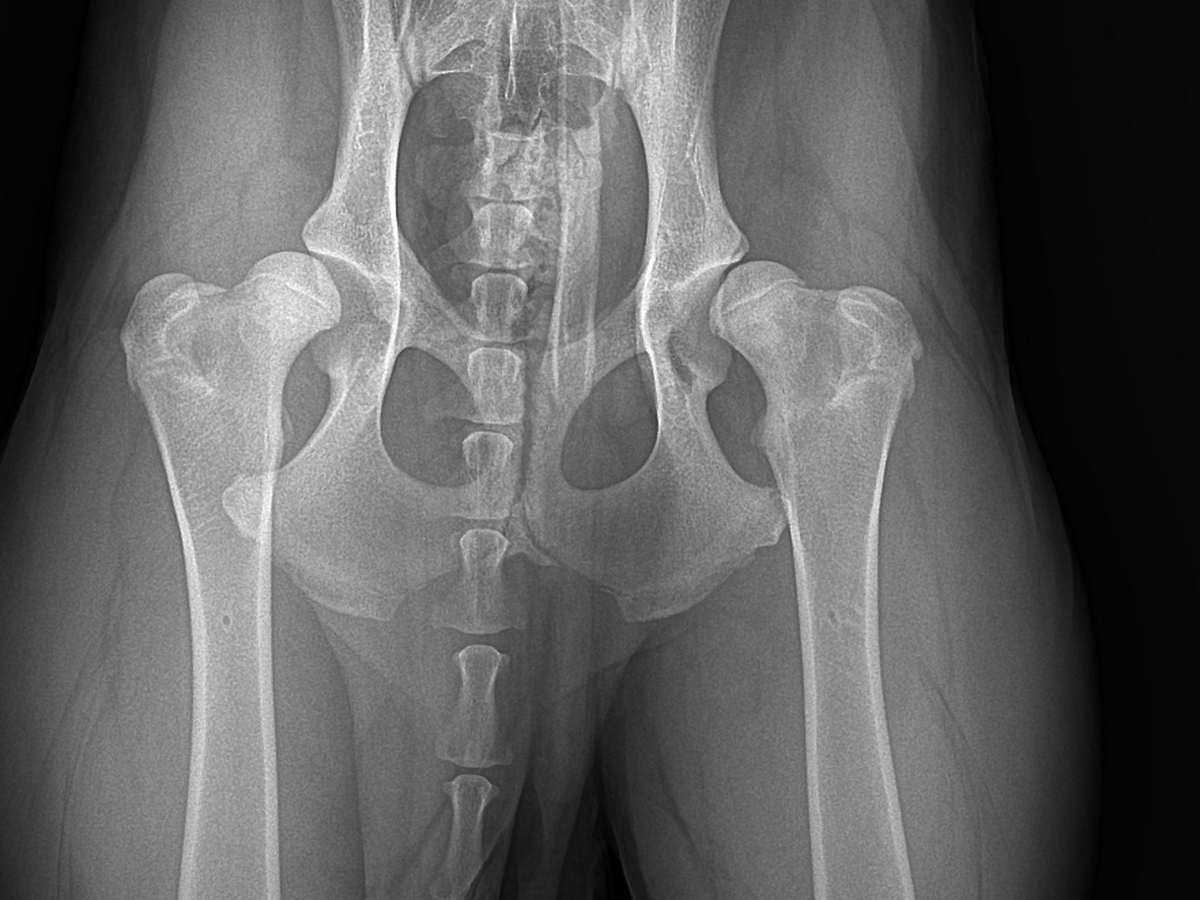

Leider musste ich früh feststellen, dass mit diesem kleinen Würmchen etwas nicht stimmt. Also mache ich einen Termin in der Tierklinik. Nach einem Röntgen seiner Hüfte wurde mein schlechtes Gefühl und schlimme Befürchtung bestätigt: Die Tierärzte haben mir mitgeteilt, dass seine Situation ernst ist und beide Seiten seiner Hüfte betroffen sind. Diese Nachricht hat mein Herz gebrochen.